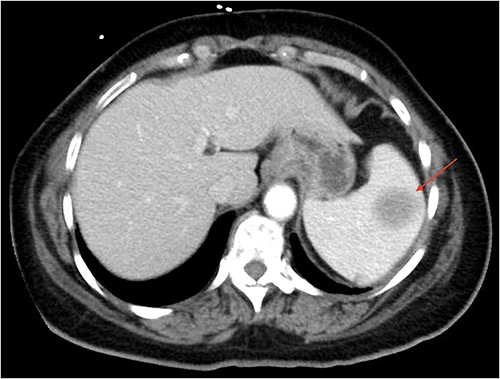

The patient was a 55-year-old female with relapsed large B cell lymphoma, severe thrombocytopenia with 17,000 platelets, and splenomegaly. Computed tomography (CT) (Fig. 1) and magnetic resonance (MR) (Fig. 2) images showed an enlarged spleen with multiple lesions, the largest measuring 3.5 cm, suspicious for lymphoma. Given the increased risk of intraoperative bleeding during splenectomy, a splenic artery embolization was performed the day before by using an Amplatzer plug (Fig. 3A and B), and platelets and fresh frozen plasma were prepared for the operation.

CT of the abdomen (axial section) showing an enlarged spleen with a 3.5 cm lesion.